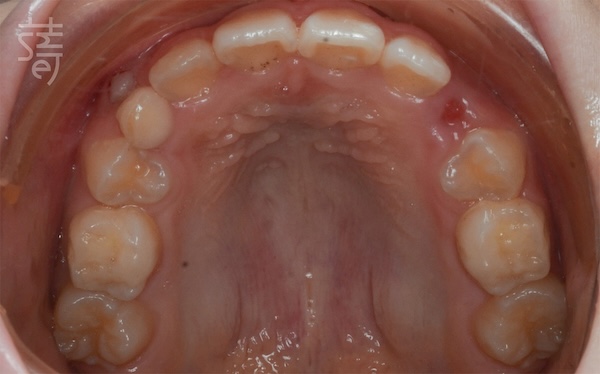

在每天固定佩戴中,牙齒悄悄往正確位置移動:前牙逐漸整齊,大臼齒被引導到更穩定的咬合,齒列在不打亂生活的狀態下,一點一滴變得更整齊。

Quietly, without disrupting school or mealtimes, Ti’s teeth began to shift: her front teeth aligned, her molars settled into a stronger bite, and her smile grew a little more confident—one aligner at a time.

兩年後回診,X 光片上清楚顯示小緹的牙列變整齊了、牙弓更開展,嘴型也能自然閉合。那些早期努力的累積,就這樣安靜卻確實地發生在孩子身上。

Two years later, Ti returned for a follow-up, and the X-rays told the story clearly: a broader arch, straighter teeth, and a relaxed, natural lip seal. The quiet, steady work of early treatment had taken root.